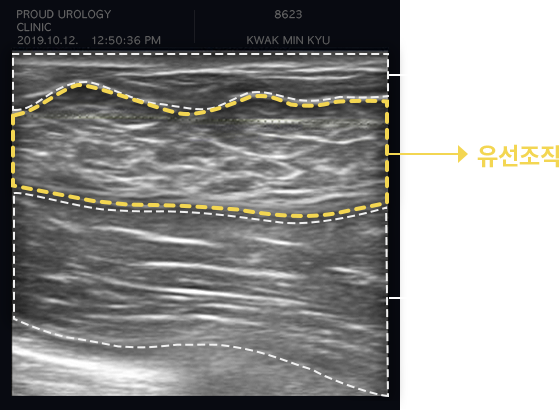

초음파를 통한 구분

하이스트는 고해상도 이미지를 구현하는 첨단 정밀 초음파

진단기(E-CUBE)를 통해

방사선 노출 없이 안전하게

유선조직 증식 여부를 정밀 검사합니다.

여유증의 유형

초음파 검사를 통해 유선조직 유무에 따라

지방형 여유증과 유선형 여유증으로 크게 나눌 수 있습니다.

(운동으로 개선 불가)